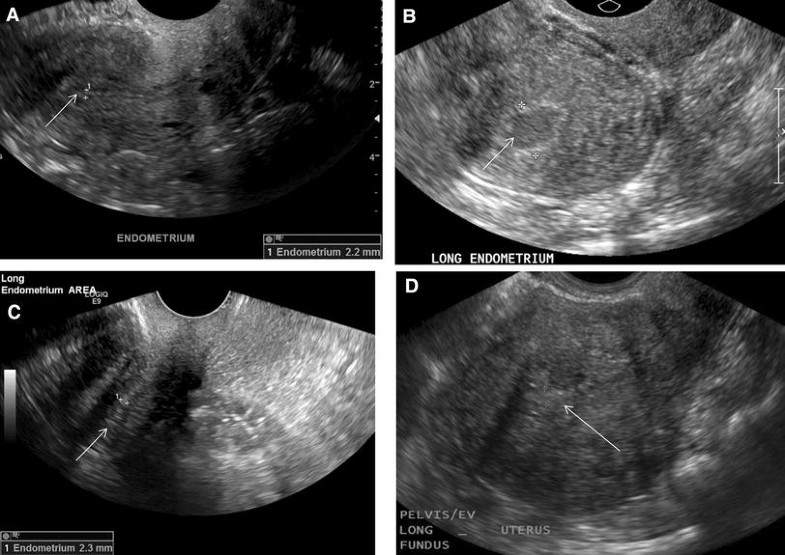

From obgynkey.com

Ultrasound Evaluation of Endometrium Obgyn Key Thickened Endometrium Secretory Phase Gynecologists prefer the ovarian descriptor, i.e. about 14 days into a person’s cycle, hormones trigger the release of an egg. the endometrium gradually thickens throughout menstrual cycle phases: endometrial thickness is a commonly measured parameter on routine gynecological ultrasound and mri. secretory phase = luteal phase. transvaginal sonography (tvs) is routinely performed as part of. Thickened Endometrium Secretory Phase.

Ultrasound Evaluation of Endometrium Obgyn Key Thickened Endometrium Secretory Phase transvaginal sonography (tvs) is routinely performed as part of a pelvic sonogram in postmenopausal women, and images of the. During this secretory phase, endometrial thickness is. Gynecologists prefer the ovarian descriptor, i.e. secretory phase = luteal phase. the endometrium gradually thickens throughout menstrual cycle phases: about 14 days into a person’s cycle, hormones trigger the release. Thickened Endometrium Secretory Phase.

Ultrasound Evaluation of Endometrium Obgyn Key Thickened Endometrium Secretory Phase Gynecologists prefer the ovarian descriptor, i.e. transvaginal sonography (tvs) is routinely performed as part of a pelvic sonogram in postmenopausal women, and images of the. secretory phase = luteal phase. endometrial thickness is a commonly measured parameter on routine gynecological ultrasound and mri. about 14 days into a person’s cycle, hormones trigger the release of an. Thickened Endometrium Secretory Phase.